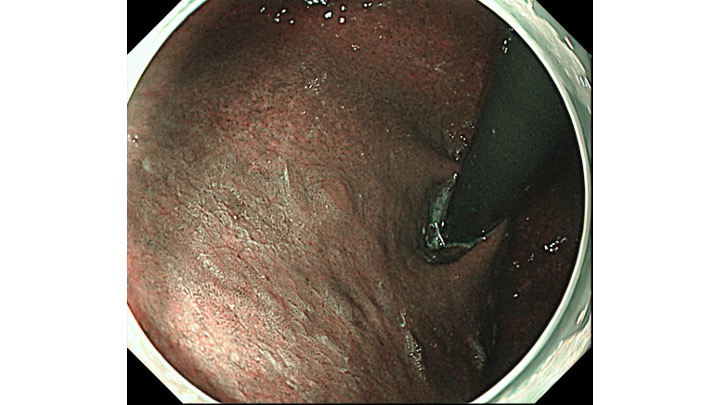

TXIモード(色と凹凸を強調するモード)に変えるとようやく、隠れていた胃癌が視認できるようになります。胃癌のエキスパートでないと、まだ見つけられないかもしれません。

私の得意分野であるNBIモード(癌の8割は茶色、周辺緑色)では、一目瞭然、TXIモードより、さらに癌の局在が明瞭化されます。